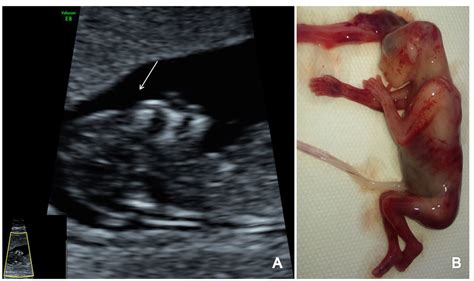

• Nuchal Translucency (NT) Measurement: This is a crucial part of the scan, where the sonographer measures the fluid-filled space at the back of the baby's neck. An increased measurement can indicate a higher risk of chromosomal abnormalities, such as Down syndrome.

• Nasal Bone Assessment: The presence or absence of the nasal bone is also evaluated, as its absence can be associated with certain chromosomal abnormalities.

• Anatomy Check: The sonographer will examine the baby's brain, spine, abdomen, and limbs to ensure proper development.